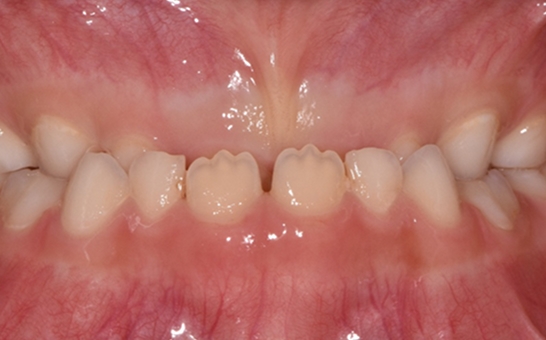

인비절라인 퍼스트(Invisalign First)는 어린이와

성장기 청소년을 위한 투명 교정 장치로, 치아와 턱뼈가

성장하는 과정에 맞춰 설계된 교정 시스템입니다.

해당하는 증상이 있다면 전문의와 상담 후 조기 교정 시

성장기 어린이에게 교합이 틀어지는것을 미리 예방 할 수 있습니다.

영구치가 나오는 과정에서

공간이 부족한 어린이

※ 바른선택치과의원은 의료법을 준수하며 위 케이스는 실제 내원 환자분의 동의하에 공개된 사진과 동일한 환자분께 같은 조건에서 촬영한 사진을 활용했습니다.

개인에 따라 진료 및 치료 방법이 다르게 적용할 수 있으며, 효과와 부작용이 개인마다 다르게 나타날 수 있는 점을 안내해 드리며, 진료 전 전문의료진과 충분한 상담을 권해드립니다.